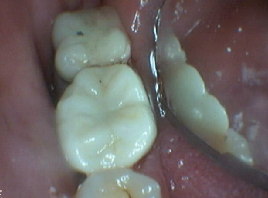

Bruxir Crowns